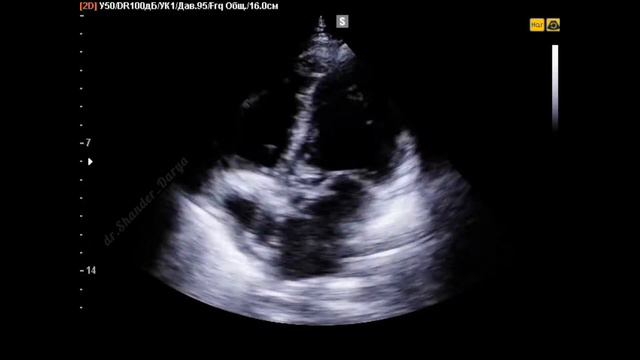

В данном видео мы покажем клинический случай: мужчина 43 лет с жалобами на одышку, утомляемость, слабость, эпизоды потери сознания. При эхокардиографии ...